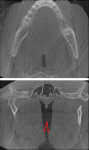

Tonsillar calcifications or tonsilloliths (13.7% of our cases) are mineral deposits accumulated in the tonsils that often appear as clusters of calcifications superficially located in the tonsillar tissues (Figure 2). Most frequently, they are seen in the palatine tonsils, bilaterally, at the level of the floor of the mouth. They are rather benign and require no action unless they are large, which is rare. Other incidental findings of low or moderate significance may be seen in Table 1.